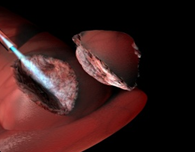

The Hemera Thulium Laser offers high-speed performance regardless of the size of the gland, vasculature and morphology. the surgeon can, then, choose whether to use vaporization, vaporesection or technical enucleation

Hemera Thulium Laser remains effective even after many passages. Thulium laser is superior due to the possibility to emit both in continuous and pulsed mode. A continuous emission with the ability to vaporesect with lower costs due to the possibility of using multiple – time reusable fibers instead of disposable ones.

Hemera Thulium Laser emits energy more efficiently and more predictably on targeted tissue, independently from their blood percentage. The optical penetration depth is uniform. The technique of laser coagulation with Hemera Thulium Laser can be performed by directing the laser beam directly on the blood flow. The side effects of postoperative bleeding and dysuria are way inferior to those of each other laser method.